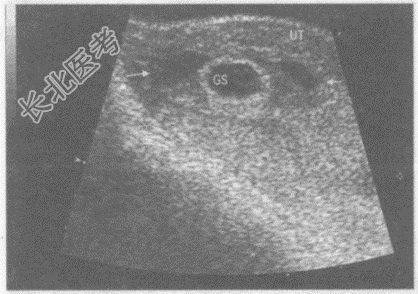

- 单项选择题临床资料:女性患者, 28岁,自述停经52天, 阴道少量出血。

超声综合描述:子宫形态饱满, 宫腔内见胎囊,内未见胎芽及胎心搏动, 可见卵黄囊回声,胎囊旁另见形态不规则无回声区。

超声提示:  A、宫腔积液

B、自然流产

C、宫内早孕(三胎)

D、宫内早孕胚胎停止发育

E、宫内早孕先兆流产胎膜后出血